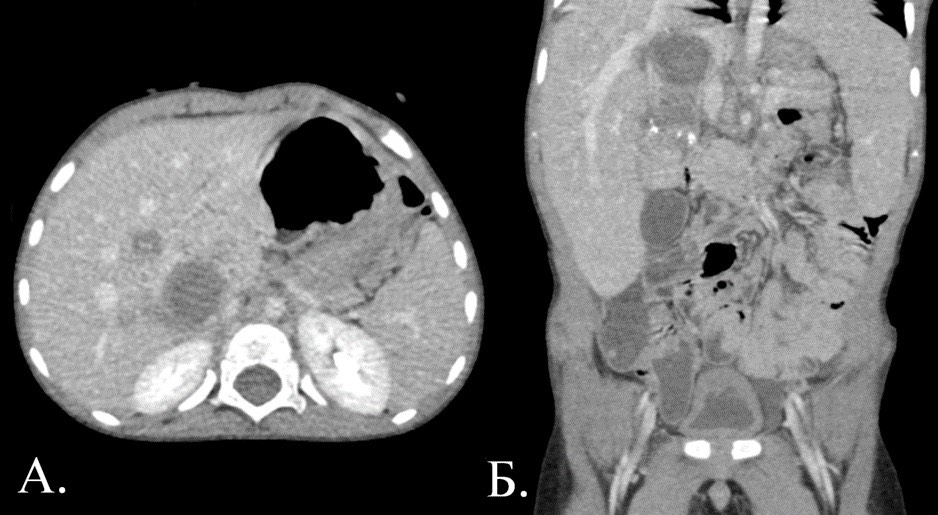

1892. Пациент 3 года (роды на 24 неделе, тяжелое течение беременности, в 2,5 года — лихорадка), альфафетопротеин — 494000 ме/мл, на КТ брюшной полости определяется объемное образование неоднородной плотности с множеством кальцинатов кистозно-солидного строения, на КТ легких — метастатический очаг в s6 правого легкого, картина соответствует